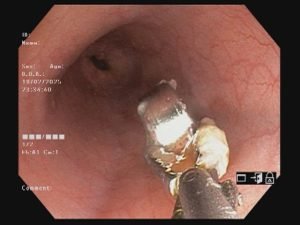

डॉ.अग्रवाल ने बताया कि प्रसिद्ध गैस्ट्रोलॉजिस्ट डॉ.निखिल गांधी से बच्चे की स्थित व एक्सरे में दिखाई देने वाले बटन बैटरी के के रूप में बताया। डॉ. गांधी ने कोठारी अस्पताल में एंडोस्कोपिक रूप से बटन बैटरी को सफलतापूर्वक निकाल दिया। डॉ.निखिल गांधी और उनकी टीम को जीवन रक्षक प्रक्रिया अपनाते हुए निस्वार्थ प्रयासों तथा डॉ.गांधी के समर्पण और विशेषज्ञता लिए उन्होंने तथा बच्चे, उसके अभिभावक ने हृदय से धन्यवाद दिया।